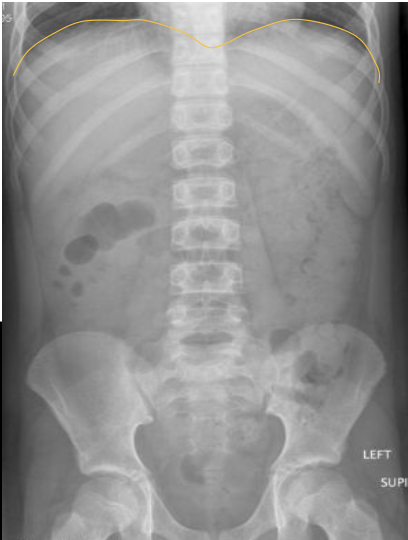

What anatomy is outlined in this image?

Diaphragm